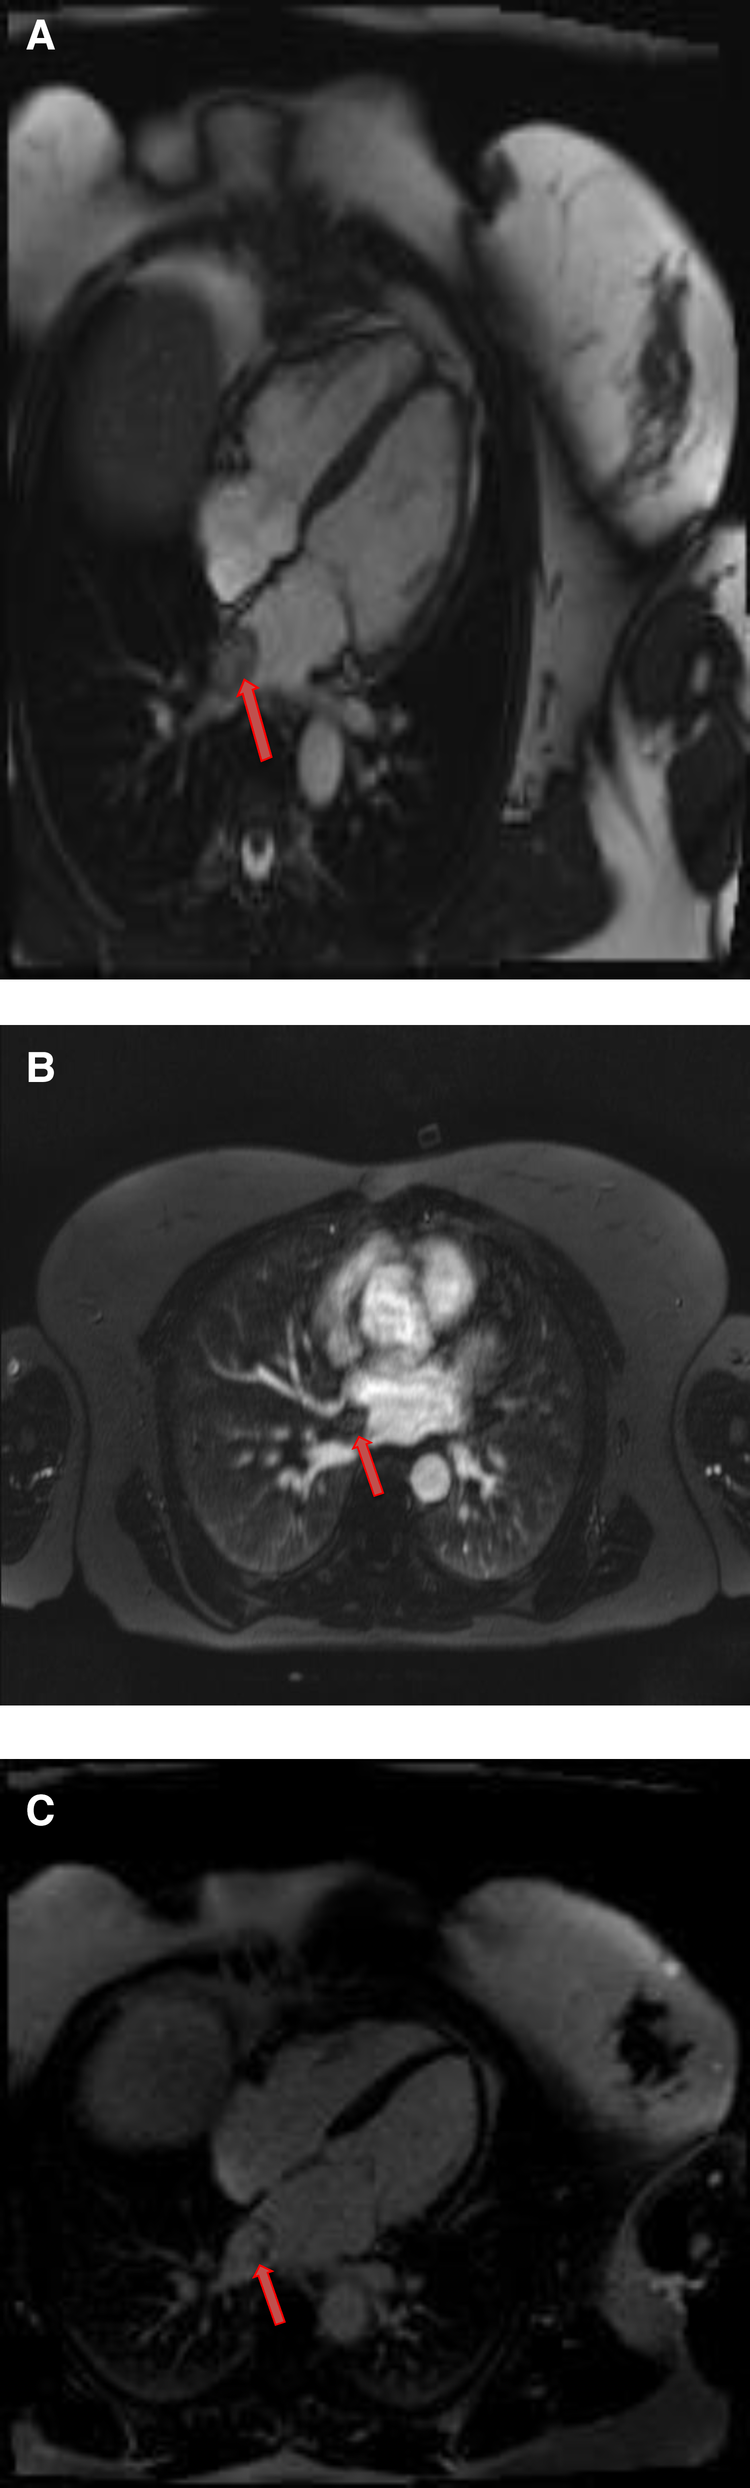

Cardiac myxomas typically have a heterogeneous appearance on CMR because of varying components of myxoid, cystic, hemorrhagic, fibrotic, and calcified material (27). As they are highly mobile tumors, cine imaging is often very helpful in the work-up of myxomas. Tumor mobility, including mitral valve prolapse causing obstruction, may be seen on the cine images. On SSFP cine sequences myxomas are usually hypointense relative to the blood pool and hyperintense relative to the myocardium (28). They are isointense/hypointense to the myocardium on T1- weighted images and hyperintense on T2-weighted images likely due to high extracellular water contents. There may be associated regions of necrosis and hemorrhage that appear hypointense on both T1- and T2-weighted images (29). Most of the myxomas demonstrate at least some mild patchy enhancement on the first pass perfusion images. Myxomas usually show moderate to high, heterogeneous enhancement on LGE images (Table 1 and Figures 3, 4). Occasionally myxomas may also exhibit a homogeneous enhancement pattern.

Figure 3

A 51-year-old female with left atrial myxoma. (A) Absence of perfusion of the lesion on first pass perfusion images (red arrow). (B) Following gadolinium administration, there is brisk, heterogeneous enhancement of this lesion on late gadolinium enhanced images (red arrow).

Figure 4

A 69-year-old female with right ventricular apical myxoma. (A) Localizer CMR images showing a small hyperintense mass in the distal RV (red arrow). (B) The mass showing high signal intensity on axial T2weighted, dark blood, double inversion recovery fast spin echo images (red arrow). (C) The mass shows absence of perfusion on first pass perfusion images (red arrow). (D) Heterogeneous enhancement of this lesion is noted on late gadolinium enhanced images. (E) There are small central areas of non-enhancement representing necrotic or hemorrhagic material (yellow arrow). RV, right ventricle.